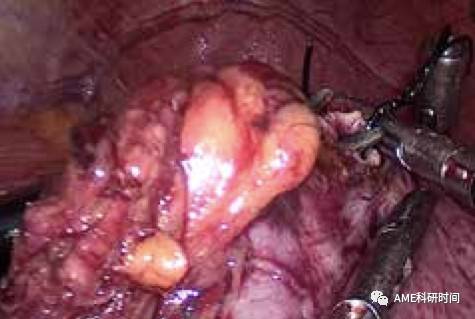

注:在Mayo Clinic学习时,发现外科医师均采用丝线进行精确测量,认为非常可取。 2食管空肠吻合:从已扩大的左上腹腋前线主操作孔放置F18号切口保护圈,置入管型吻合器杆把,将保护圈包绕吻合器并旋转、向外提拔,避免气腹漏气(如图33);远端空肠置入管型吻合器,与食管下端的钉座吻合(如图34-35), 留置或不留置胃管至空肠Y襻,空肠盲端用直线切割闭合器闭合。

管型吻合器怎么用完全腹腔镜下全胃切除术后的消化道重建——7种食管空肠吻合方法_https://www.jmylbn.com_新闻资讯_第33张

图33 保护圈包绕

管型吻合器怎么用完全腹腔镜下全胃切除术后的消化道重建——7种食管空肠吻合方法_https://www.jmylbn.com_新闻资讯_第34张

图34 置入弯管吻合器

管型吻合器怎么用完全腹腔镜下全胃切除术后的消化道重建——7种食管空肠吻合方法_https://www.jmylbn.com_新闻资讯_第35张

图35 与钉钻头嵌合

注:1)吻合时特别需要助手反向牵拉吻合口输出端肠管(如图36),避免吻合肠管重叠,造成输出肠管钉闭的严重并发症(如图37);2)本步骤中,在腹腔外把空肠套入管型吻合器,并用丝线捆绑也是可行的方法(如图38)。但需要较大的辅助切口、游离过多Roux-en-Y肠袢、手术步骤复杂化,也出现过回纳腹腔时肠管脱落和击发后丝线不能割断的情况。3)采用完全腹腔内置入并管型吻合器(F25号)进行吻合,均可顺利快捷完成。4)吻合完成后,建议放入胃管、或用剥离子通过空肠残端检查吻合口。